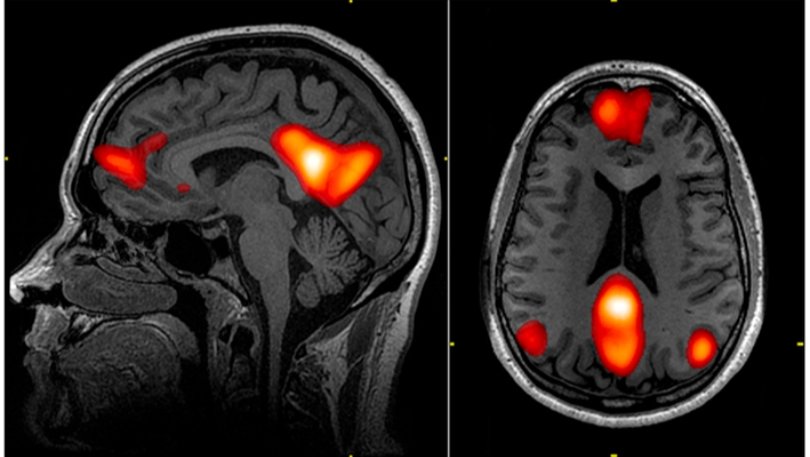

Default Mode Network (DMN) — Beynin dinlenme hâlinde aktif olan büyük ölçekli ağının fMRI görüntüsü.

Dikkat Dağınıklığı mı, Ağ Yönetimi mi?

Beynimiz tek parça çalışan bir organ değil. Farklı ağlar var. Mesela biri görev yaparken aktif oluyor, biri dinlenirken.

Bazı araştırmalar, DEHB’de bu ağlar arasındaki geçişlerin daha düzensiz olabileceğini gösteriyor. Özellikle “zihnin boşta dolaştığı” ağ (default mode network) görev sırasında tam olarak kapanmayabiliyor.

Kafanın içi sürekli açık sekmelerle dolu bir tarayıcı gibi.